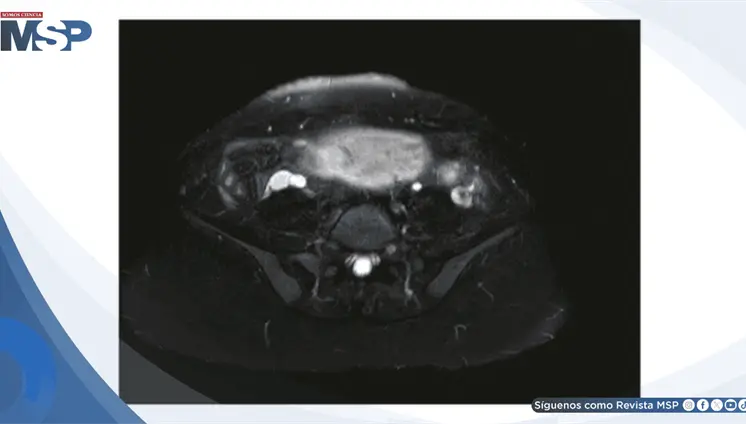

La mujer de 71 años, con antecedentes de histerectomía total y salpingooforectomía izquierda hace 30 años, presentó distensión abdominal progresiva y aumento de peso durante cuatro años.

Se confirmó un embarazo intrahepático de 23 semanas, una condición extremadamente rara en la que el feto se desarrolló dentro del lóbulo hepático derecho, con irrigación directa de la arteria hepática y una placenta firmemente adherida al tejido del hígado.